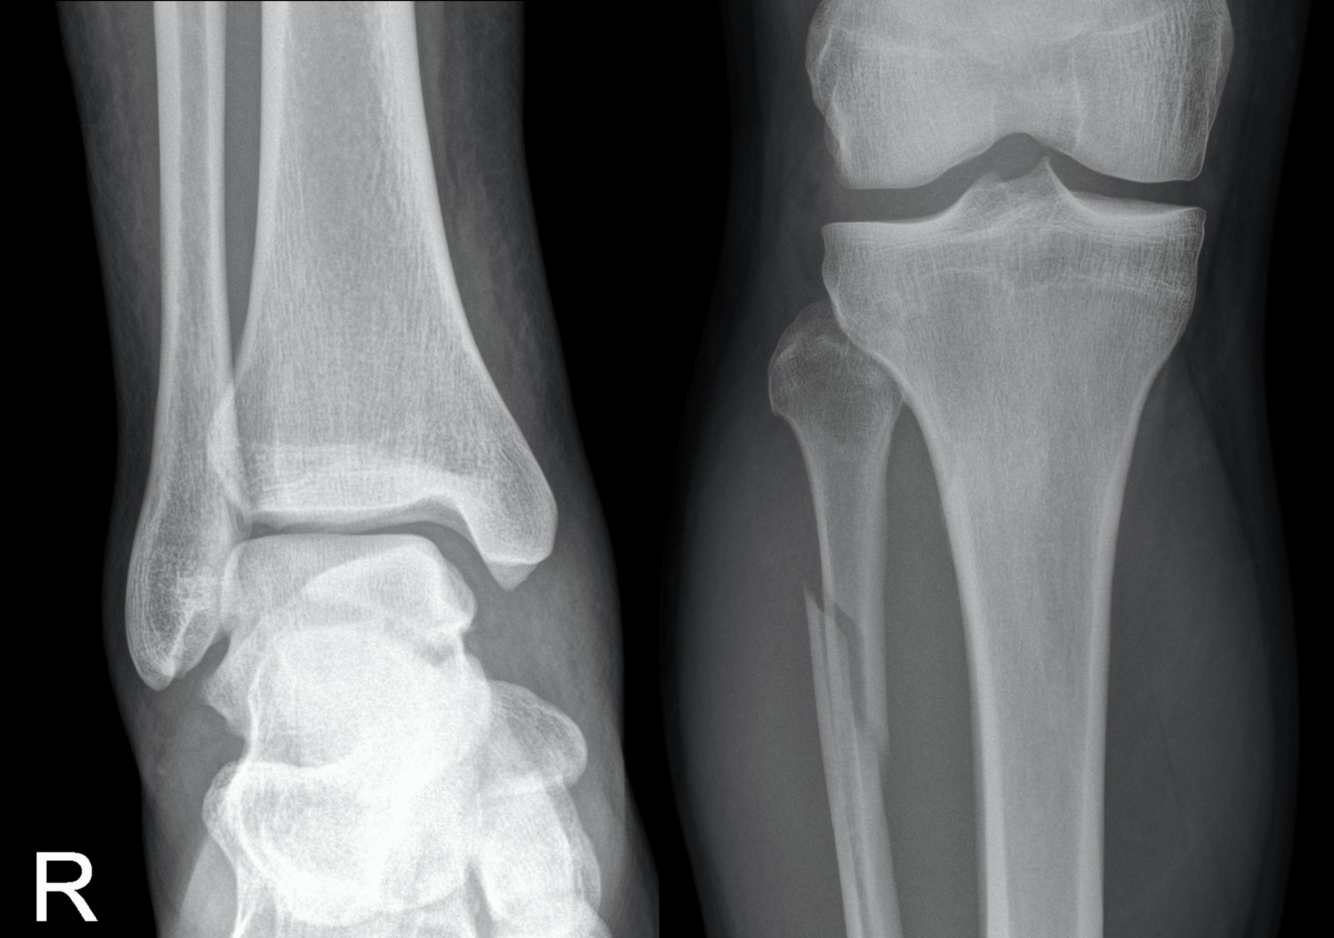

BOSWORTH

- Fracture-dislocation of the ankle resulting in the fibula being entrapped behind the tibia

- Produced by severe external rotation force applied to the foot; physical examination reveals foot severely externally rotated in relation to the tibia